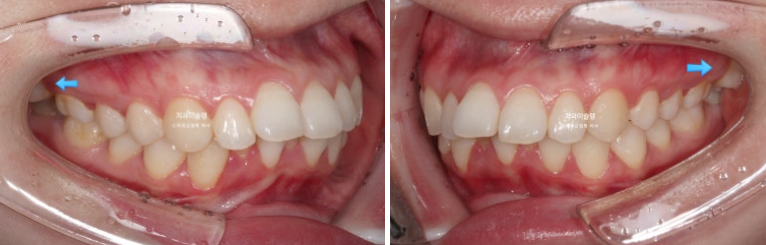

파란 화살표 부분은 위 아래 큰어금니가 엇갈려 물리는 가위교합입니다.

파란화살표 두번째 큰어금니가 바깥으로 밀려나가 가위교합이 된 것 입니다.

파란 화살표 부분의 가위교합이 개선이 되면서 어금니 교합은 물샐틈 없는1급 교합관계를 보입니다.